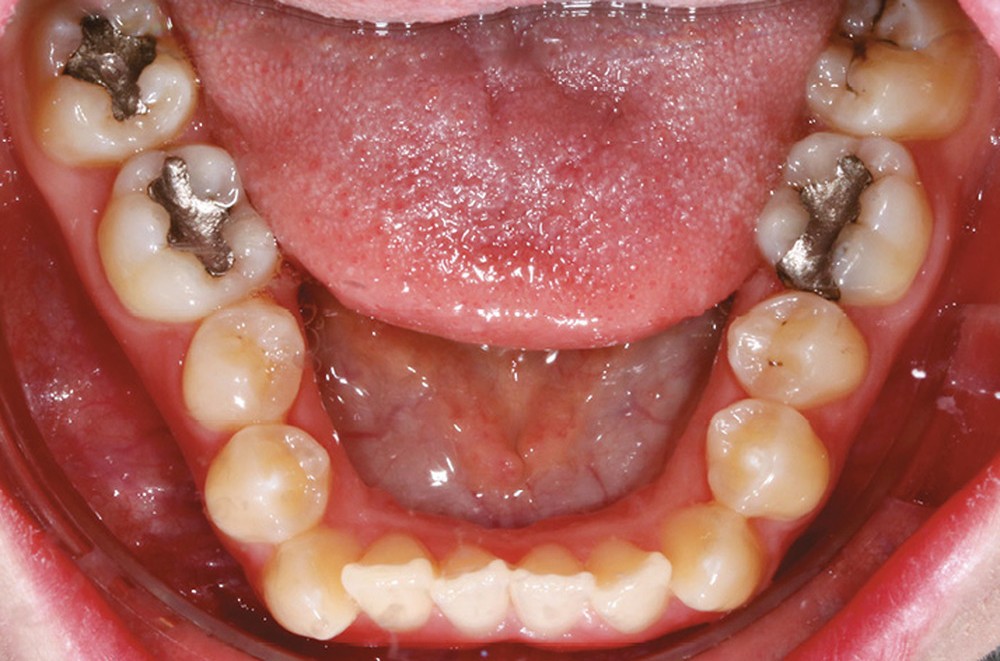

Sur le plan dentaire, on note l’absence des canines maxillaires permanentes sur l’arcade et la persistance de 63. Il existe une DDD par défaut maxillaire (indice de Bolton antérieur 90,2 %) due à l’absence des canines sur l’arcade, mais aussi à une dysharmonie de forme des dents maxillaires (fig. 2a-e).